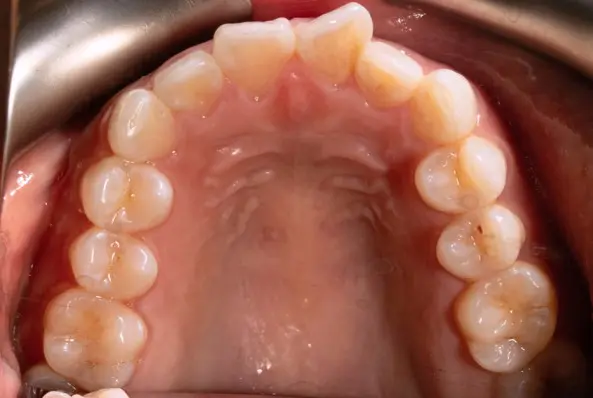

Crowding

Before